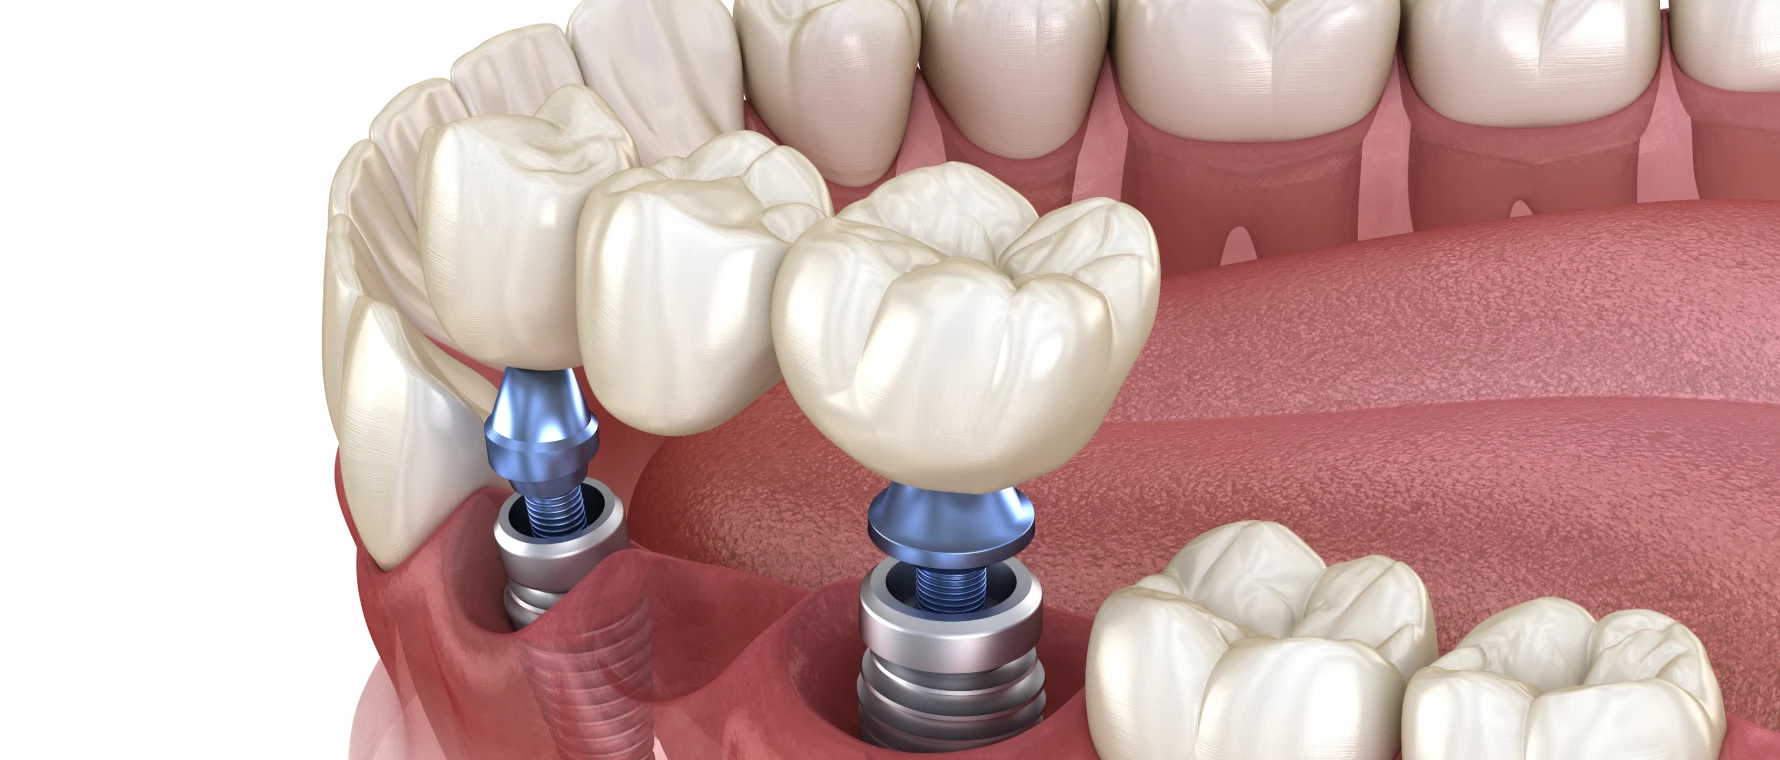

Bridge sur implants

Lorsque les dents voisines sont absentes ou fragiles, des implants peuvent servir de piliers artificiels. Cette solution évite de toucher aux dents naturelles.

Avantage : préservation des dents saines.

Inconvénient : nécessite une chirurgie implantaire préalable.

Très résistante et entièrement blanche, la zircone combine les avantages mécaniques et esthétiques. Elle est souvent utilisée pour les bridges sur implants.